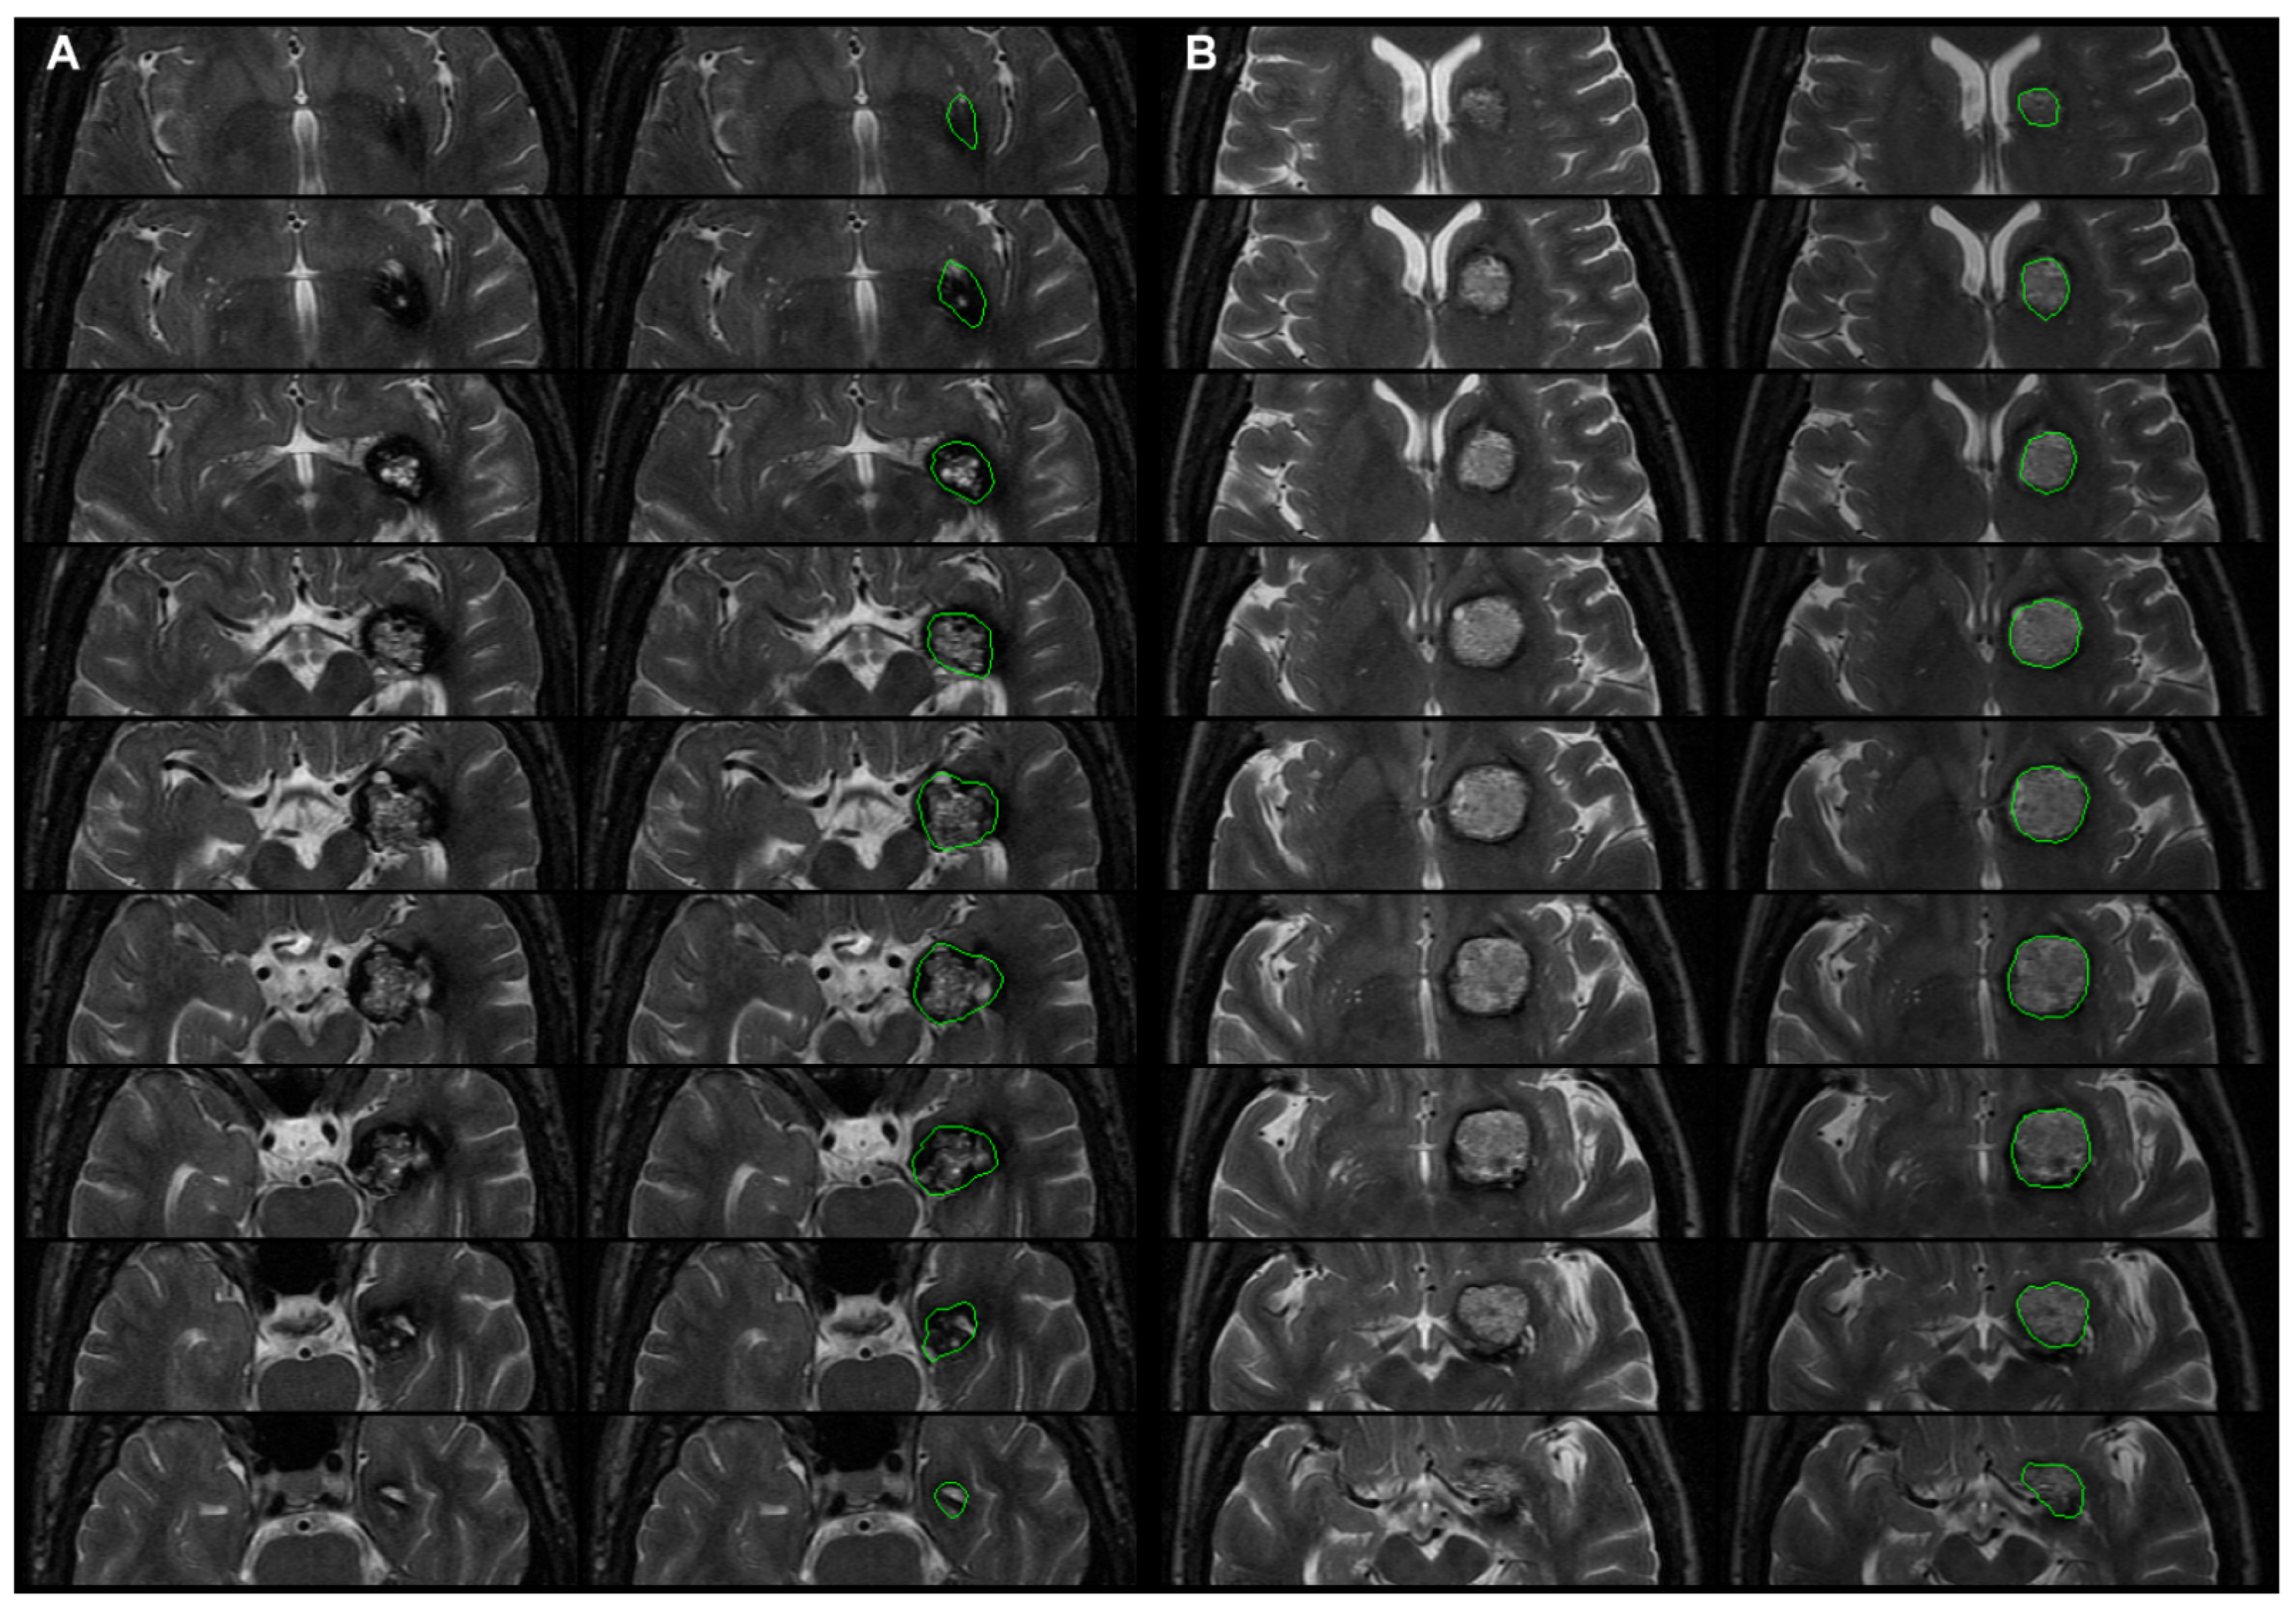

- Step P3. Manual delineation of the CCM

- Step P4. Normalizing T1WI and CCM image labels to the MNI space